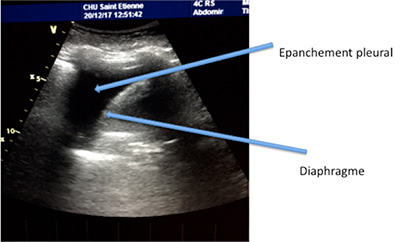

Grâce aux ultrasons, l’exploration de la plèvre se fait sans irradiation ni geste invasif. On peut déceler les pneumothorax (air dans la plèvre), les pleurésies (liquide dans la plèvre) (photo 11) ou repérer une masse ou un nodule pulmonaire au contact de la plèvre (photo 12)

Ensuite on peut réaliser une ponction très précise grâce au guidage de l’échographie